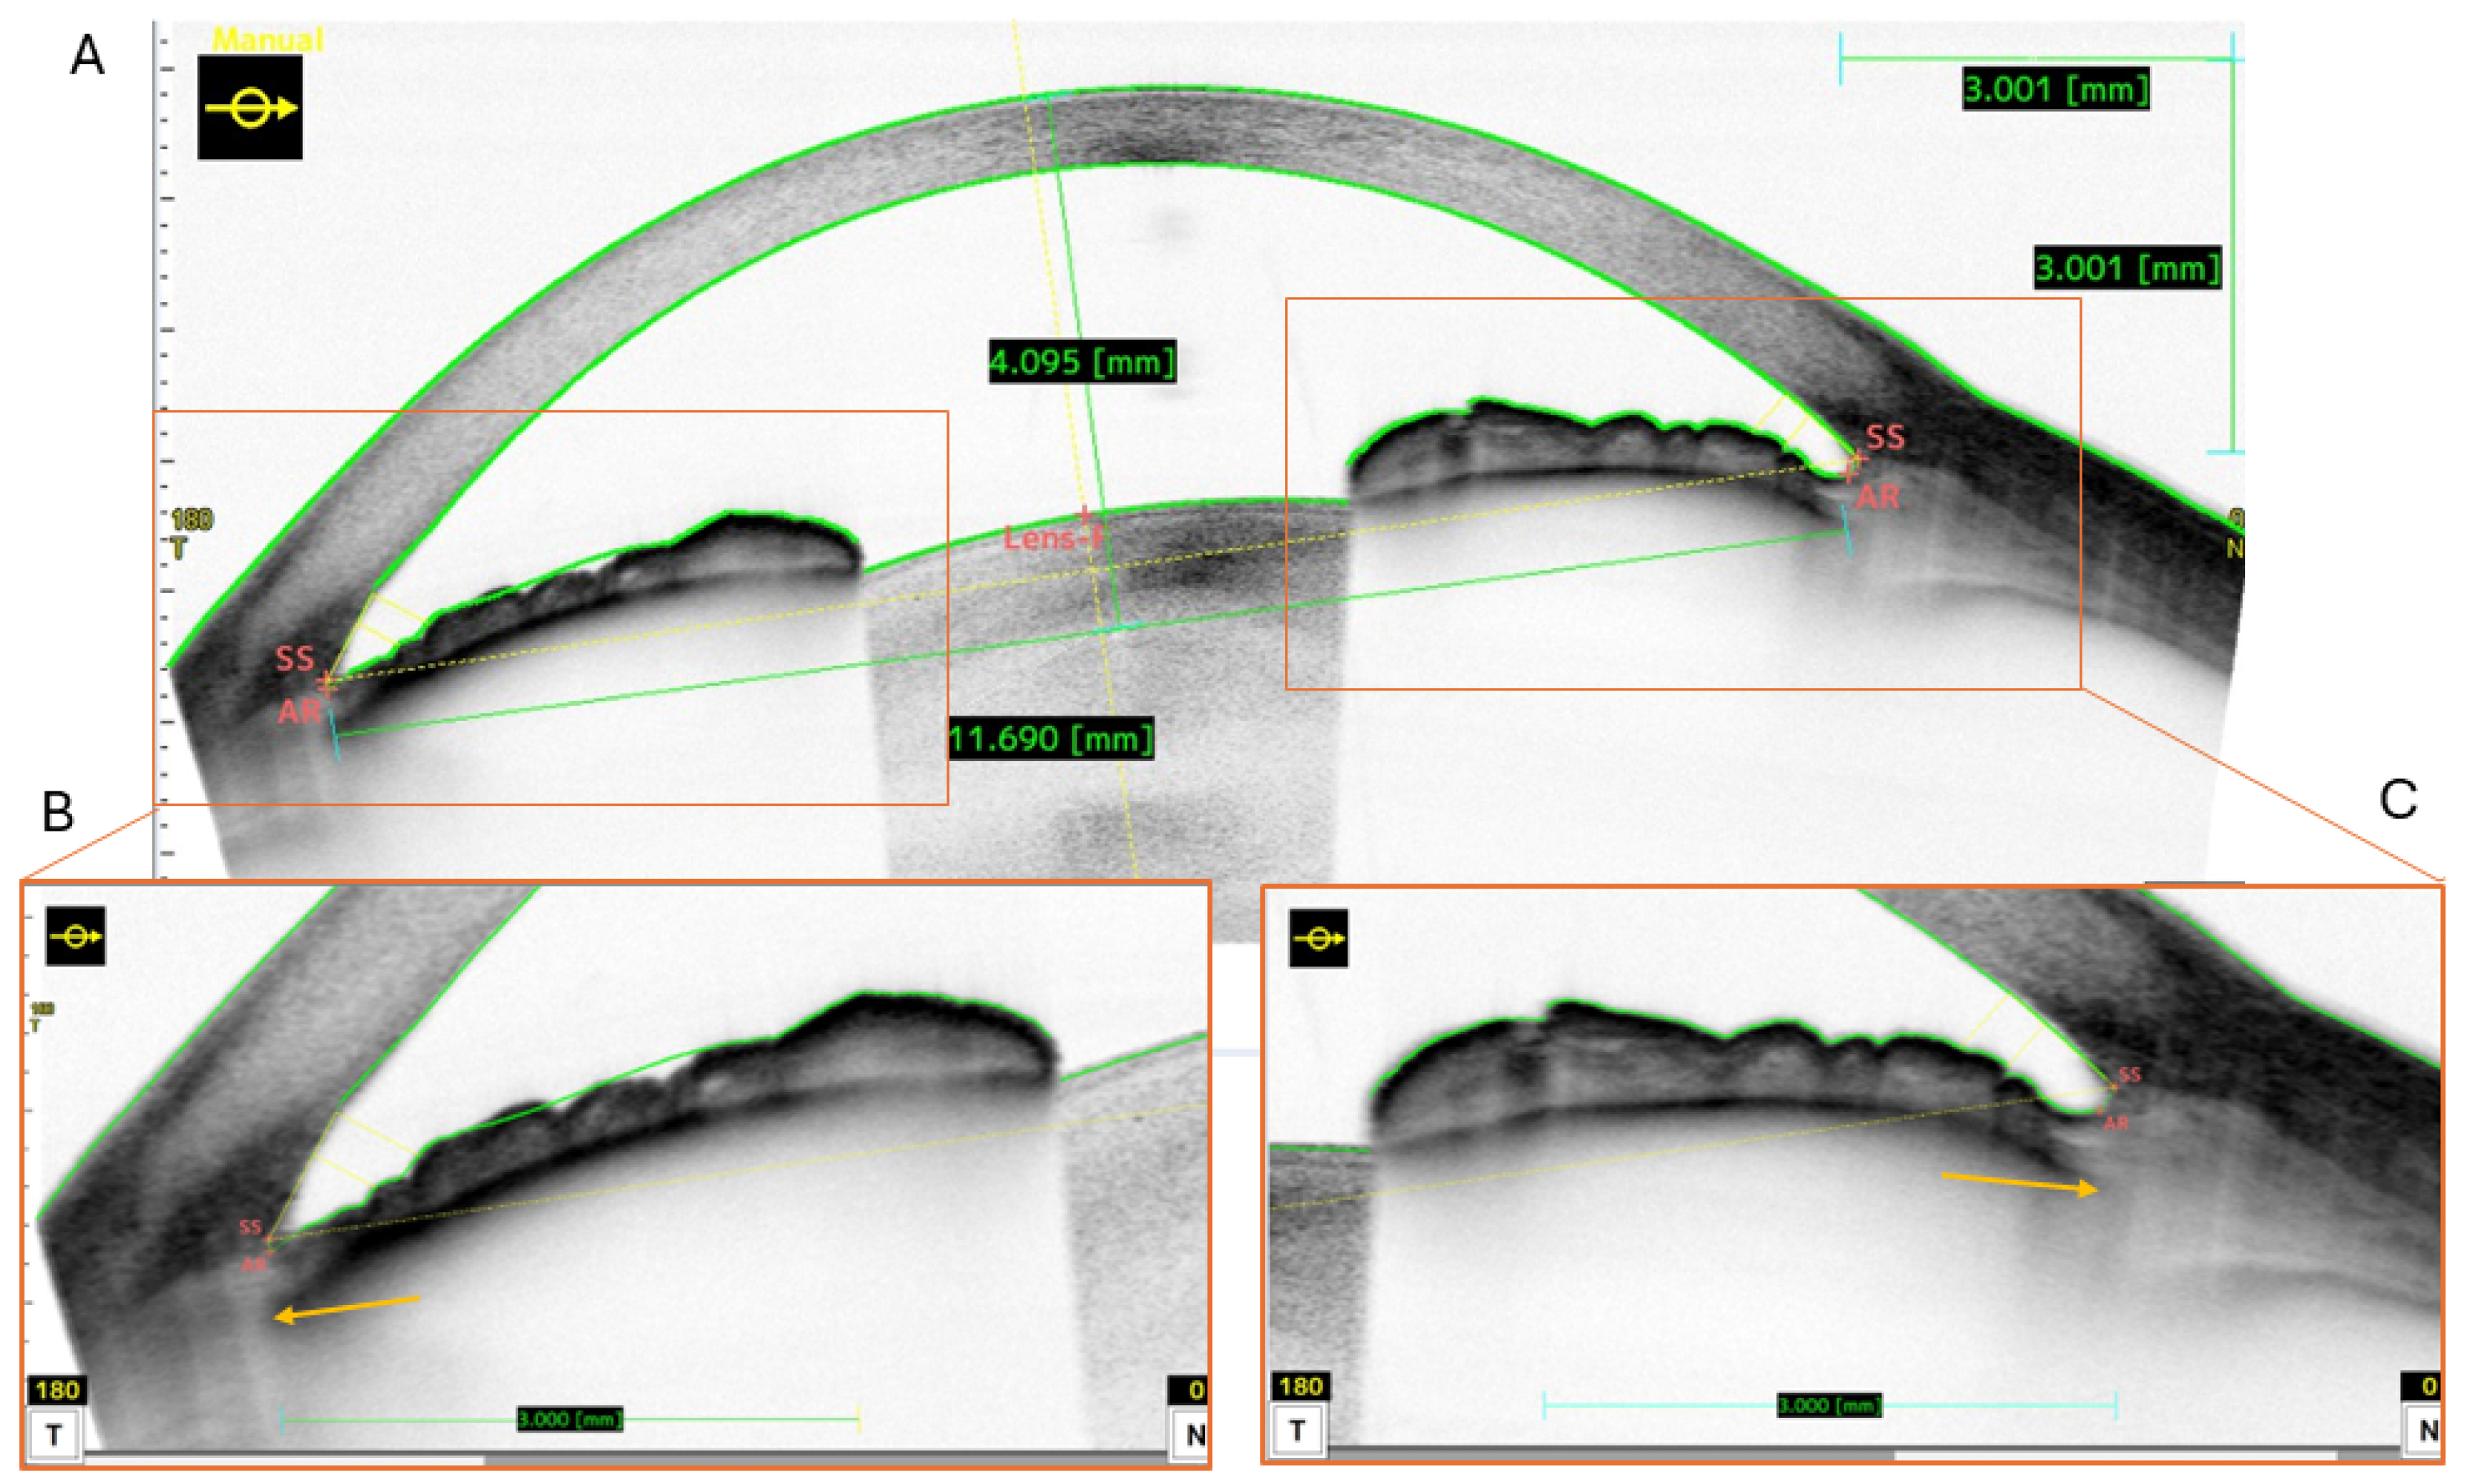

2.2. Measurement Method